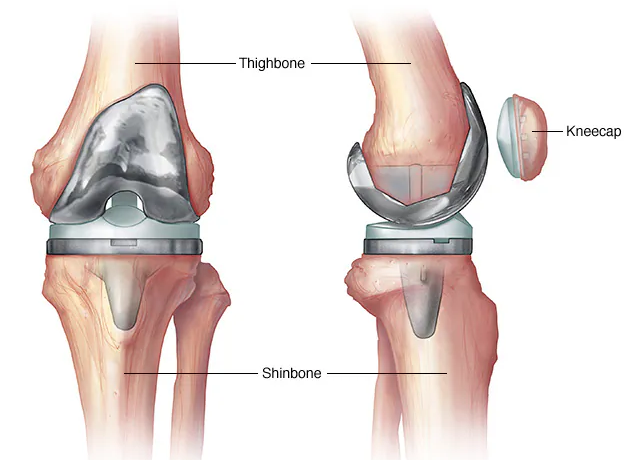

What is ACL Reconstruction? ACL reconstruction is a keyhole (arthroscopic) surgery done to restore stability of the knee after an ACL tear.

The torn ligament is replaced with a tendon graft, commonly taken from the patient’s own hamstring or peroneus tendon. Knee instability or giving-way Sports injuries Associated meniscus or cartilage…